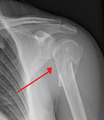

Surgical neck

The surgical neck is a narrow area distal to the tubercles that is a common site of fracture. It makes contact with the axillary nerve and the posterior humeral circumflex artery.